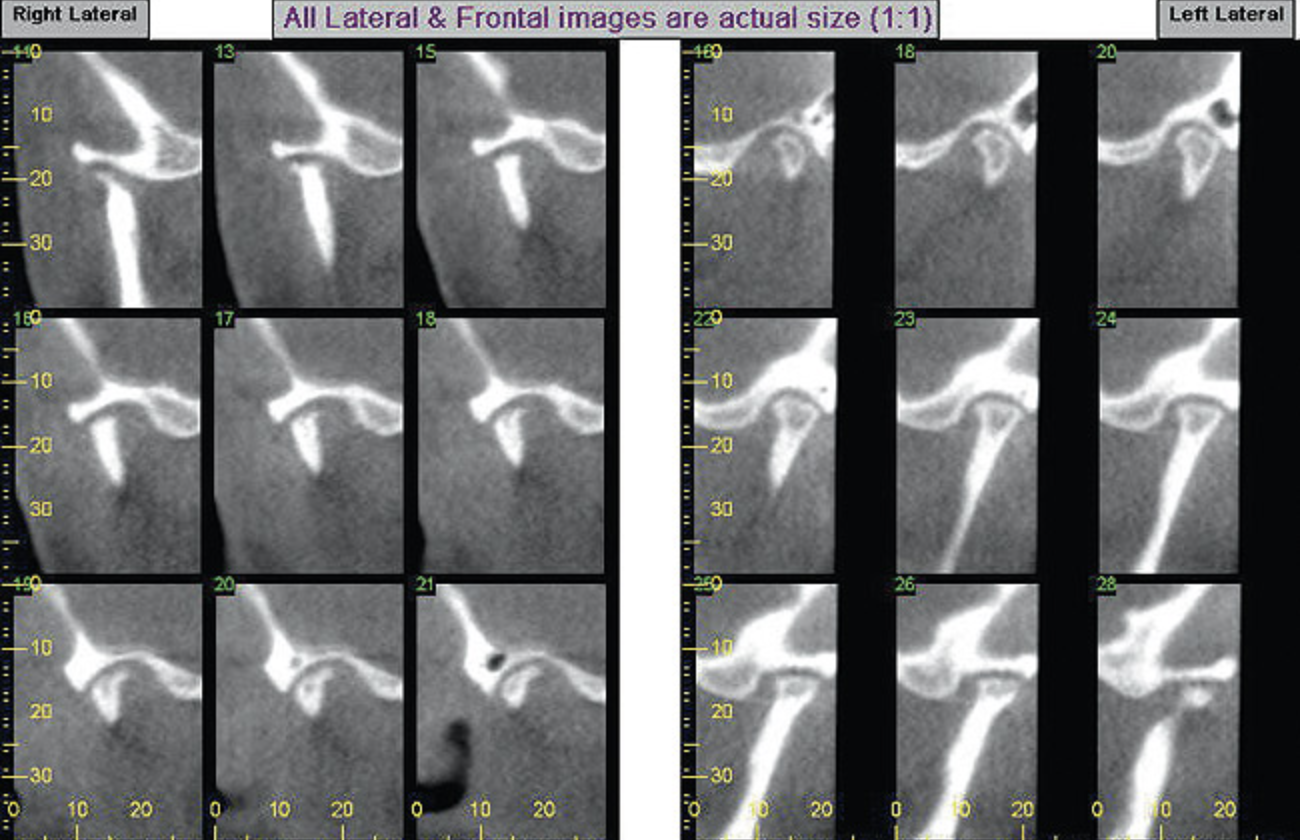

While most orthodontists appreciate anterior dental esthetics, some do not consider that the posterior teeth also have a normal alignment angle. The posterior teeth axial line angles appear to converge from the gingival through the occlusal toward a “central fulcrum.7 Alignment of teeth with significant crowding without extractions may cause a flaring of the axial alignment of both anterior and posterior teeth. If orthodontists do not extract teeth or reduce the width of teeth with interproximal reduction when the dental arch perimeter is greater than the skeletal arch perimeter, the teeth will be tipped, creating a “flared” appearance. Tipped teeth are not only esthetically unappealing, they are not centered in bone and do not allow occlusal forces to be directed down the long axis of the root, which impairs long-term stability (Figure 4). If treatment goals cannot be reached without extractions, then extractions must be considered.

Figure 4A  Coronal section of 3D tomograph revealing axial alignment of posterior teeth. A) Dental alignment does not allow occlusal forces to be directed down long axis of teeth. Maxillary teeth had been tipped to the buccal to compensate for the transverse discrepancy. B) Teeth are positioned to allow occlusal forces to be directed down long axis of teeth.

Figure 4A

Figure 4B  Coronal section of 3D tomograph revealing axial alignment of posterior teeth. A) Dental alignment does not allow occlusal forces to be directed down long axis of teeth. Maxillary teeth had been tipped to the buccal to compensate for the transverse discrepancy. B) Teeth are positioned to allow occlusal forces to be directed down long axis of teeth.

Figure 4B